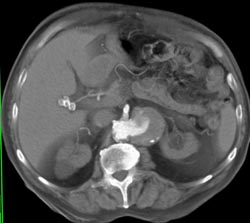

Diagnosis

Hepatic Congestion